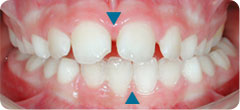

After palatal expansion, the mandible is centred and the upper and lower midlines are aligned (see blue triangles). The mandible can now grow normally.